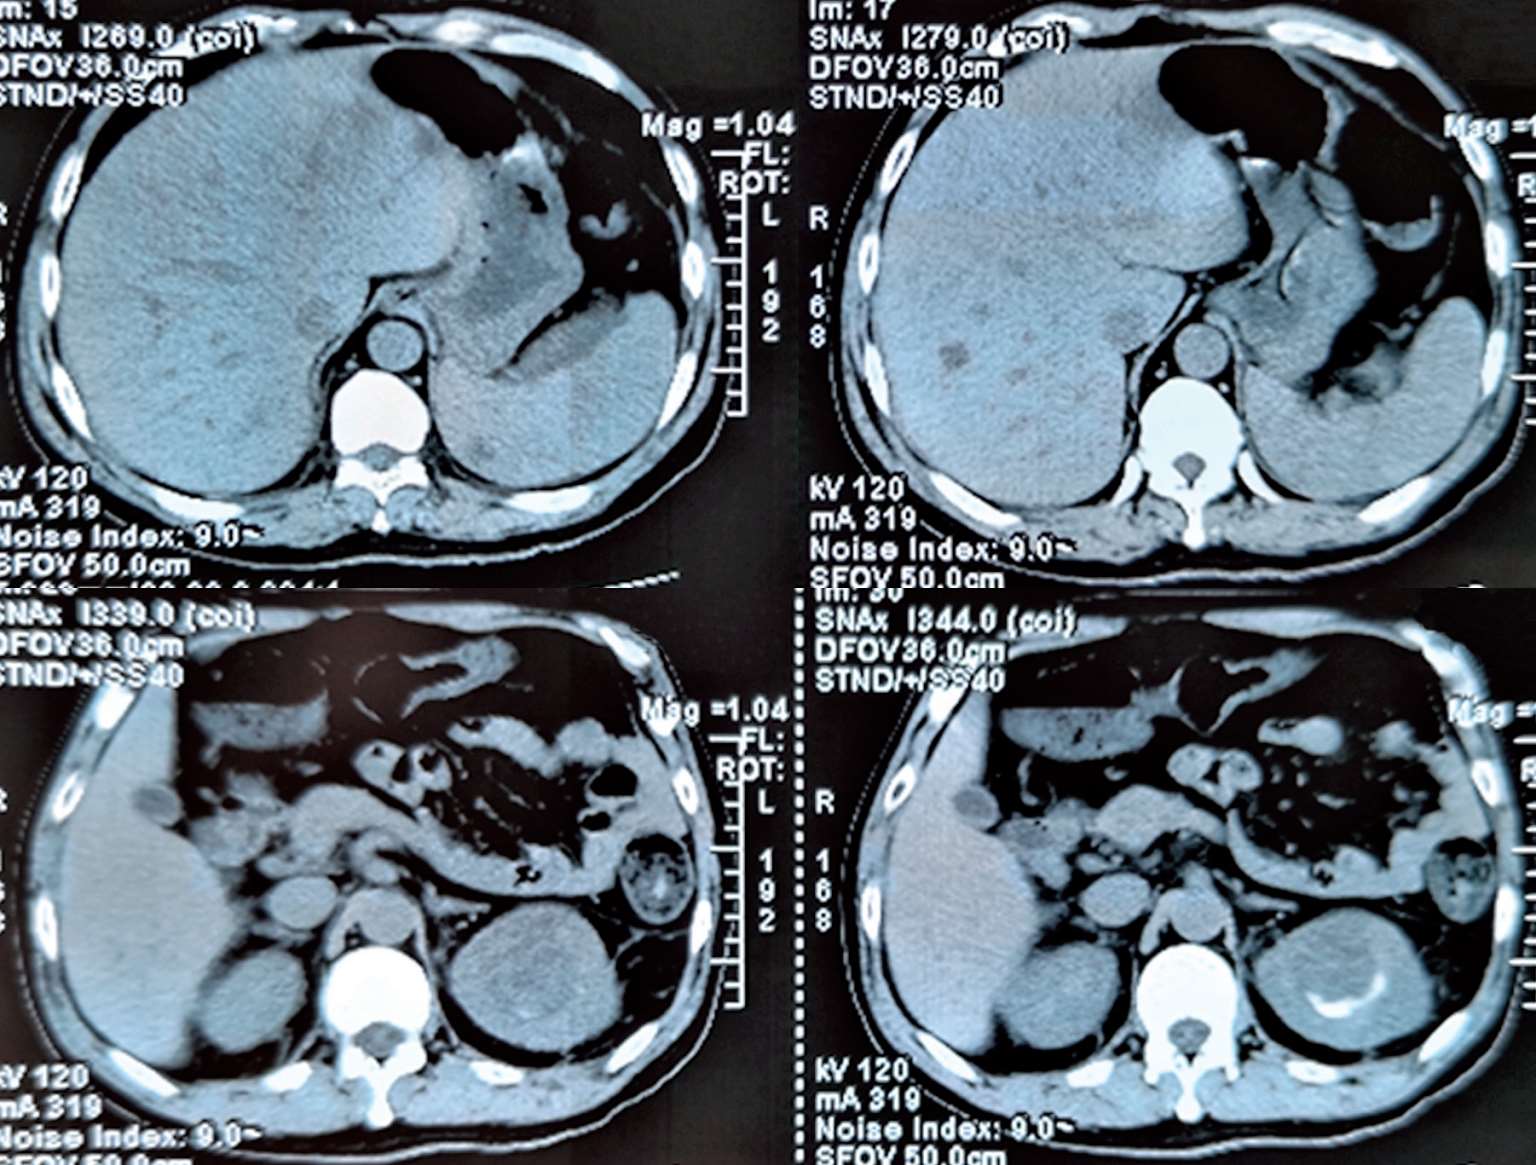

2018年7月12日晨家人发现患者倒地,当时呼之能应,精神萎靡,但四肢瘫软无力,胡言乱语,大小便失禁。至江苏省当地人民医院就诊,体温39.2℃,伴颈强直,脑膜刺激征阳性,肺部可闻及少许啰音。胸部CT(图2-1)示“右下肺见类圆形团块状稍高密度影,其内见气体影,右肺上叶近空洞样稍高密度影,周围见胸膜牵拉,胸膜不规则增厚。头颅CT示:脑内多发斑点状、小片状模糊密度影”。腹部CT(图2-2)示:肝脏、脾脏数枚小低密度影,肛周、脾周少许包裹性积液;左肾上极占位。给予布洛芬口服退热,但患者出现神志模糊,对答不切题,伴有可疑的癫痫发作,请神经内科会诊后考虑结核不能排除,遂转至南通市某医院呼吸科就诊。追问病史,患者起病前两周曾有上呼吸道感染病史,表现为少许咳嗽咳痰。

图2-1 2018年7月13日肺CT平扫:右下肺见类圆形团块状稍高密度影,其内见气体影,右肺上叶近空洞样稍高密度影,周围见胸膜牵拉,胸膜不规则增厚

图2-2 2018年7月13日腹部CT平扫:肝脏、脾脏数枚小低密度影,肛周、脾周少许包裹性积液;左肾上极占位